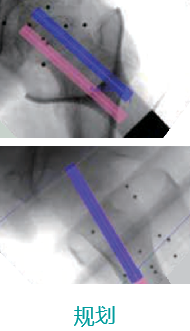

天玑II 辅助小儿股骨颈骨骺滑脱内牢靠术

基本情形:患者男,,,,,,,12岁,,,,,,,跛行一年,,,,,,,加重一周

机械人辅助优势:入钉偏向和骨骺接壤精准定位

病例泉源:北京积水潭医院